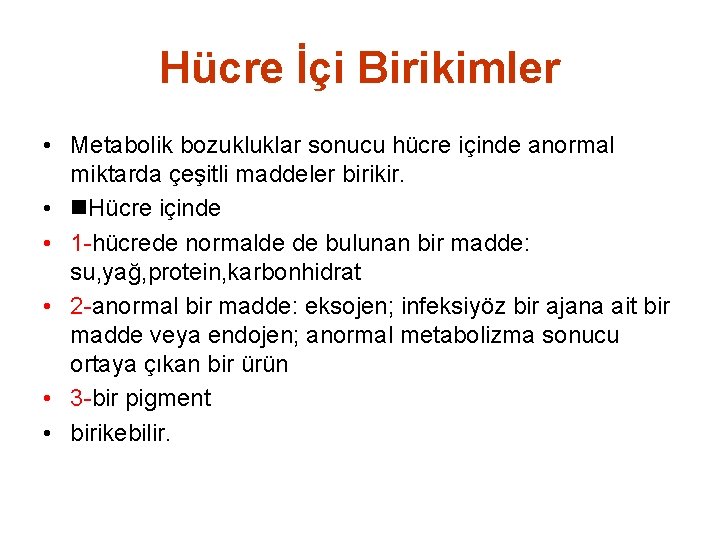

Hücre İçi Birikimler • Metabolik bozukluklar sonucu hücre içinde anormal miktarda çeşitli maddeler birikir. • Hücre içinde • 1 -hücrede normalde de bulunan bir madde: su, yağ, protein, karbonhidrat • 2 -anormal bir madde: eksojen; infeksiyöz bir ajana ait bir madde veya endojen; anormal metabolizma sonucu ortaya çıkan bir ürün • 3 -bir pigment • birikebilir.